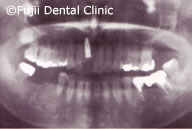

他院にて抜歯、歯を削らずに治療を希望ということで来院されました。インプラント埋入後、8週程度で補綴物を(クラウン)装着。経過観察を行いました。治療後も、虫歯や歯周病を予防するため、唾液検査を行い、予防プログラムを作成して、定期的に検査をしています。

| 初診時口腔内写真およびインプラント埋入後パノラマ写真 |